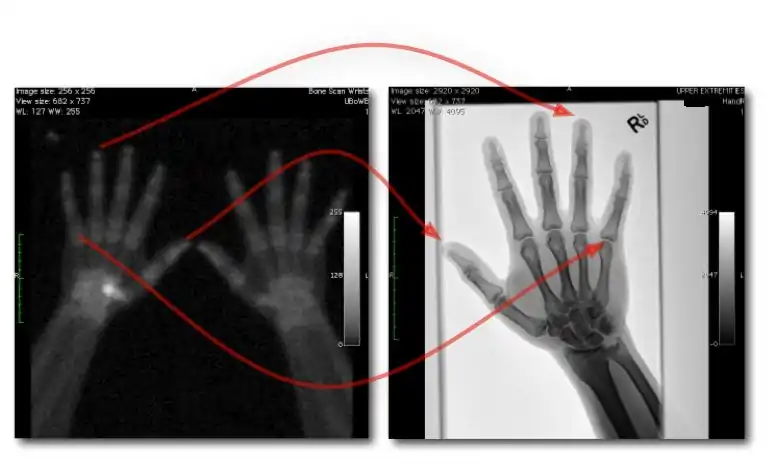

Dual-Energy Imaging